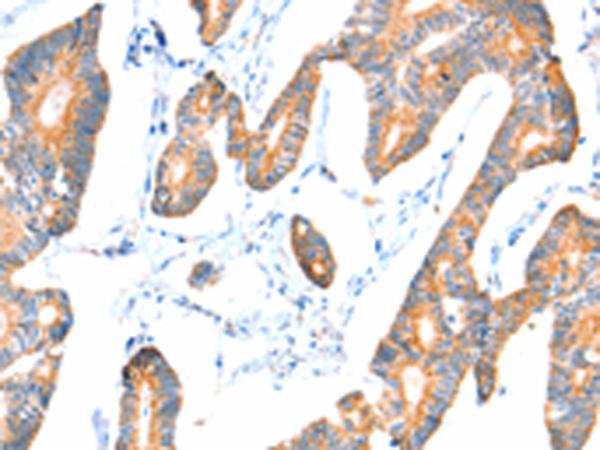

The image on the left is immunohistochemistry of paraffin-embeddedHuman lung cancer tissue using(VANGL1 Antibody) at dilution 1/20

The image on the left is immunohistochemistry of paraffin-embeddedHuman colon cancer tissue using (VANGL1 Antibody) at dilution 1/20